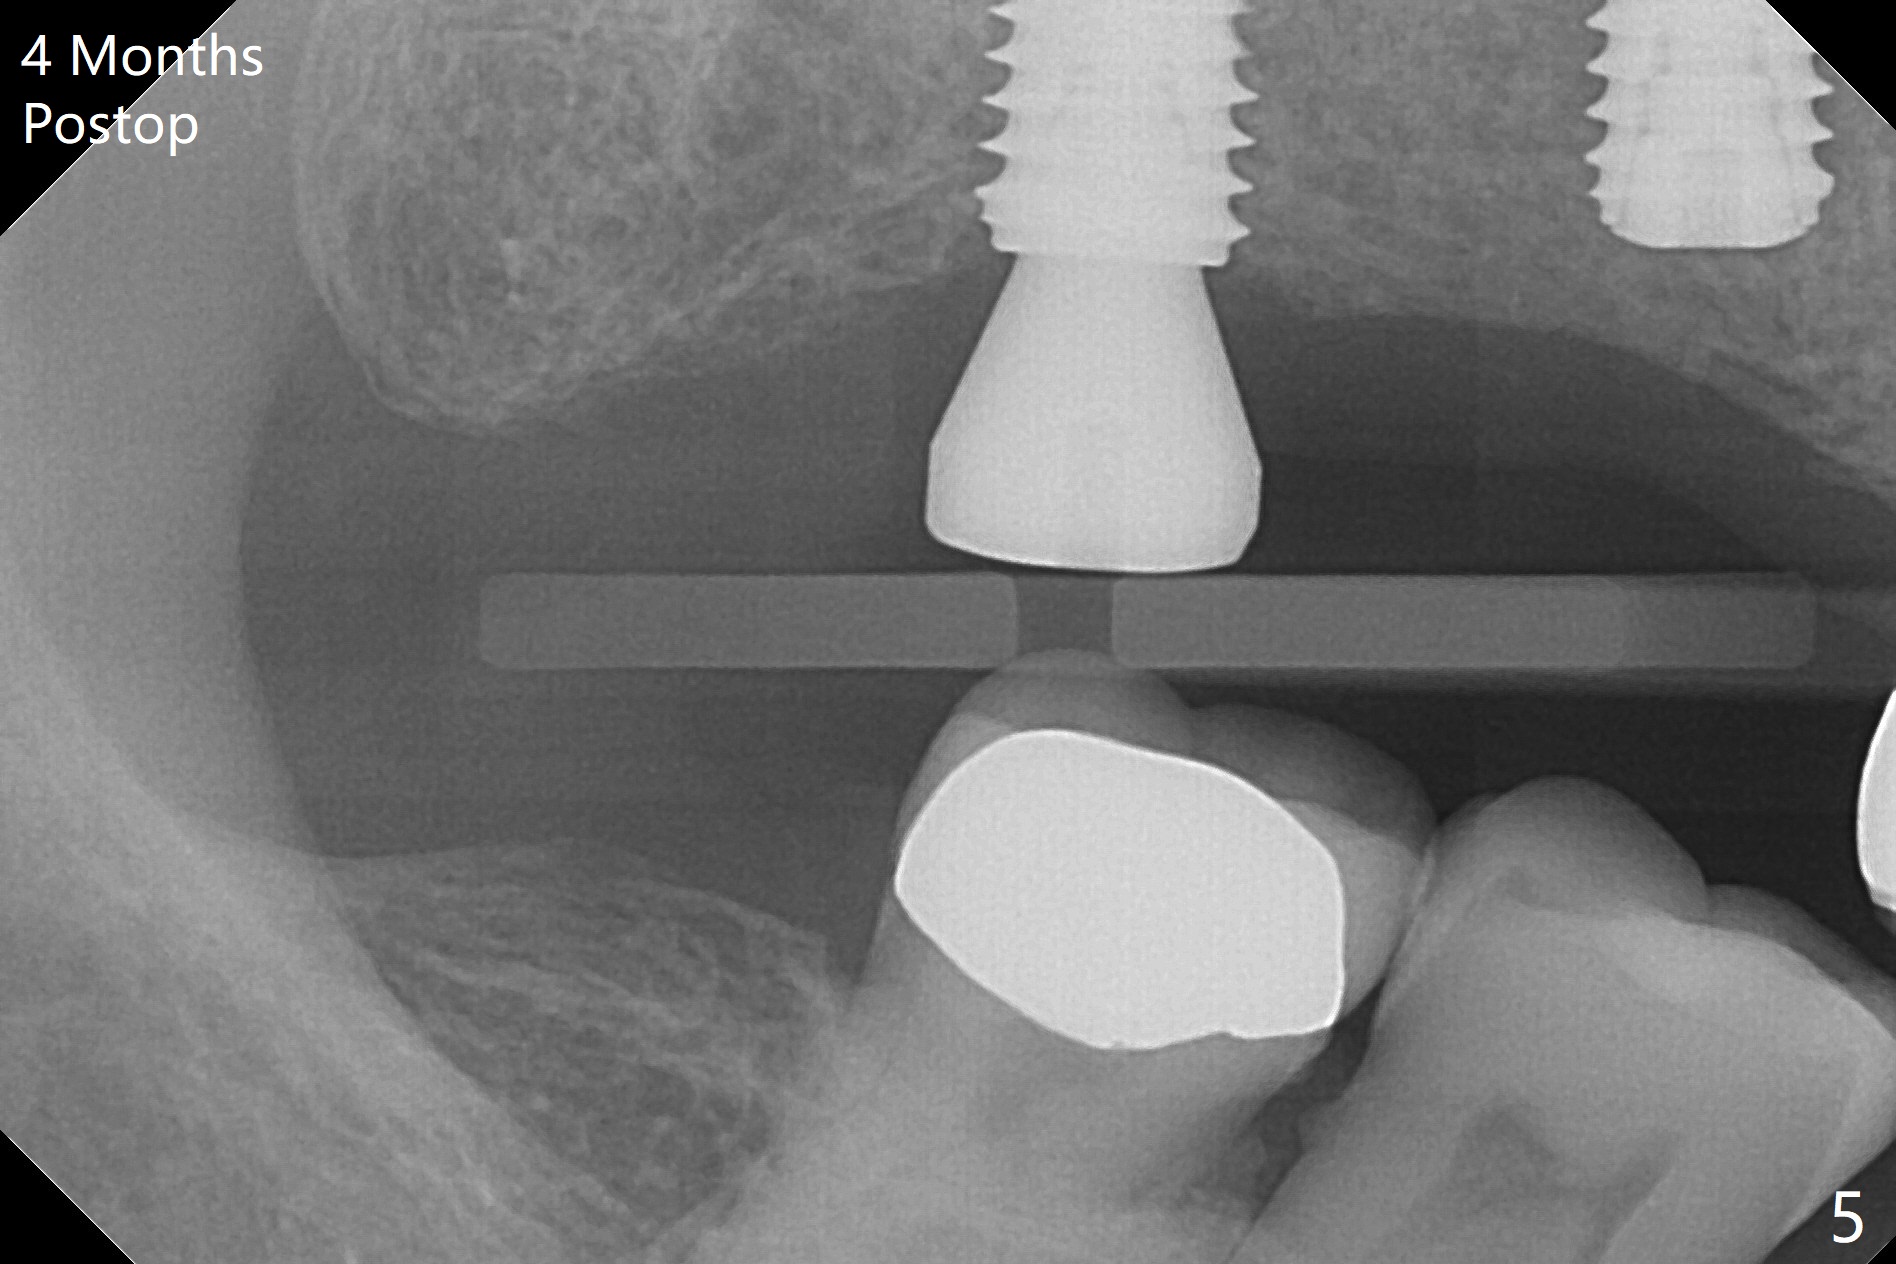

Osteotomy at the sites of #2 and 3 goes on as planned. Sinus lift using DIO 2.8 mm round bur with 6 and 7 mm stoppers (respectively) is carried on without certainty, because it is difficult to feel the stop through the osteotomy. The crest may be uneven or soft. It appears that the soft tissue landmark as a stop may be easier to identify. In fact a 3 mm IBS Magic Expander (an osteotome) was used for sinus lift at #3. The 2 implants are placed with 20 and 30 Ncm (Fig.1,2). Healing abutments are inserted. At 2-week follow-up, the patient reports "pain a few days earlier, took a pill of antibiotic, pain gone. UR metal is sharp". She does not take antibiotic regularly. Exam reveals that there is heavy plaque around #2,3 healing abutments. The buccal edge of #2 abutment is trimmed for comfort. Nearly 1 month postop, #3 healing abutment dislodges with buccal gingival erythema and edema with purulent discharge (Fig.3). Healing screw is placed at #3 with Amoxicillin and Chlorhexidine prescribed. One week later, the implant at #3 turns when the healing screw is retightened (Fig.4). After debridement, Vanilla graft is placed. There is no infection at #2 or 3 four months postop (Fig.5,6); the lingual gingiva is erythematous and edematous at #29 with mobility II (Fig.7 (vertical root fracture)). Uncover is conducted at the site of #3; there is no infection superficial 7.5 months postop (Fig.8). There is a large buccal defect upon incision with dark hemorrhage. In fact the bone density is low crestally (Fig.8 *). Bone graft is placed for the 2nd time. Eleven months later (1.5 years post implant placement), the bone regrows crestal (Fig.9 *). The crown at #3 is loose 1 year 5 months post cementation (Fig.10). After proximal trimming (Fig.11 *), the abutment at #3 is seated completely. After lab repair, crown oral cement, crown/abutment removal for excess cement removal, the crown/abutment cannot be torqued >25 Ncm (Fig.12, 30 Ncm). PA shows incomplete seating (Fig.12 <). Then the crown is sectioned so that the abutment has more freedom to be seated completely with pressure against the gingiva (the patient feels pain, Fig.13). Torque is 30 Ncm. After crown cementation, the abutment will not be removed for cement removal.